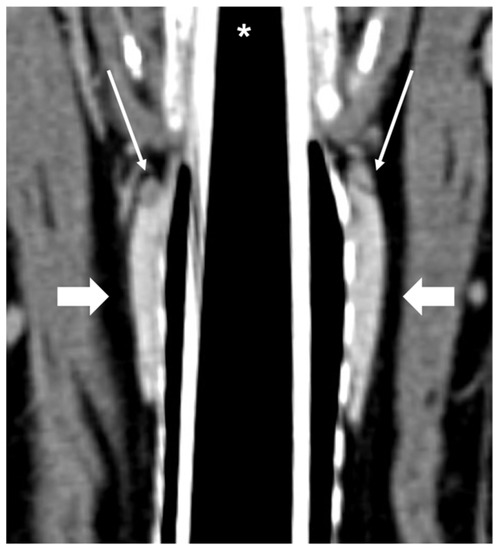

Figure 6.

CT appearance of parathyroid gland hyperplasia. Post-contrast dorsal (A) and right parasagittal (B) CT reconstruction of one dog with parathyroid gland hyperplasia (arrow) at the level of the right internal parathyroid. The parathyroid is ovoid-shaped and homogeneously contrast-enhancing. Note the marked difference in attenuation between the parathyroid (hypoattenuating) and the adjacent thyroid tissue.